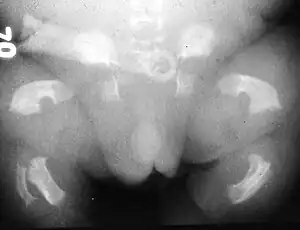

| Radiogram of a baby born with thanatophoric dwarfism | |

Thanatophoric dysplasia (thanatophoric dwarfism) is a severe skeletal disorder characterized by a disproportionately small ribcage, extremely short limbs and folds of extra skin on the arms and legs.

Infants with this condition have disproportionately short arms and legs with extra folds of skin. Other signs of the disorder include a narrow chest, small ribs, underdeveloped lungs, and an enlarged head with a large forehead and prominent, wide-spaced eyes. Thanatophoric dysplasia is a lethal skeletal dysplasia divided into two subtypes. Type I is characterized by extreme rhizomelia, bowed long bones, narrow thorax, a relatively large head, normal trunk length and absent cloverleaf skull. The spine shows platyspondyly, the cranium has a short base, and, frequently, the foramen magnum is decreased in size. The forehead is prominent, and hypertelorism and a saddle nose may be present. Hands and feet are normal, but fingers are short. Type II is characterized by short, straight long bones and cloverleaf skull.[1] It presents with typical telephone-handle shaped long bones and H-shaped vertebrae. :)

Infants with type 1 thanatophoric dysplasia also have curved thigh bones, flattened bones of the spine (platyspondyly) and shortened thoracic ribs. Note: Prenatal ultra-sound images of the ribs sometimes appear asymmetrical when in fact they are not. In certain cases, this has caused a misdiagnosis of Osteogenisis Imperfecta (OI) type II.